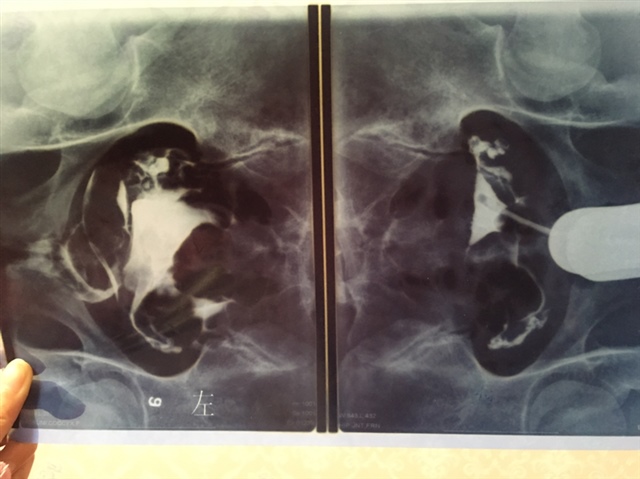

右边图是造影前 左边图是造影剂流入宫腔之后的成片 造影剂分布扩散均匀看着不是输卵管堵塞 如果是炎症输液吃药消炎就好 听取医生的建议

H💍J[帖主]:好的,这样一解释我好像知道怎么看图了,谢谢😊